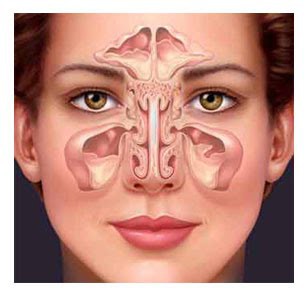

é o médico que trata das doenças dos ouvidos, nariz e garganta, muitas vezes chamado apenas de "otorrino".

Os sinais e sintomas mais comuns dessas doenças são:

Obstrução nasal

Dor de cabeça (cefaléia)

Dor na face

Secreção nasal

Sangramento nasal (epistaxe)

Dificuldade auditiva/surdez

Zumbido

Tontura

Secreção no ouvido (otorréia)

Sangramento no ouvido (otorragia)

Dor de ouvido (otalgia)

Dor de garganta

Rouquidão (disfonia)

Roncos